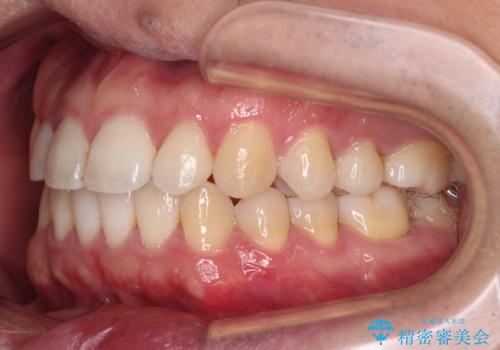

インビザラインで奥歯の咬み合わせと前歯のデコボコを改善

- 前歯のデコボコと奥歯の咬み合わせを気にして来院された患者様です。

前歯のデコボコはインビザラインで十分に対応可能と判断できましたが、咬合力が強いため、臼歯(特に右側)の交叉咬合はインビザライン単体では困難と思われました。

まずはインビザライン単体で矯正治療を開始し、交叉咬合が改善されない場合にはアンカースクリューなどの使用を検討することとしました。

インビザライン単体では右側の交叉咬合を解消することができなかったため、アンカースクリューを併用して咬合を改善させました。